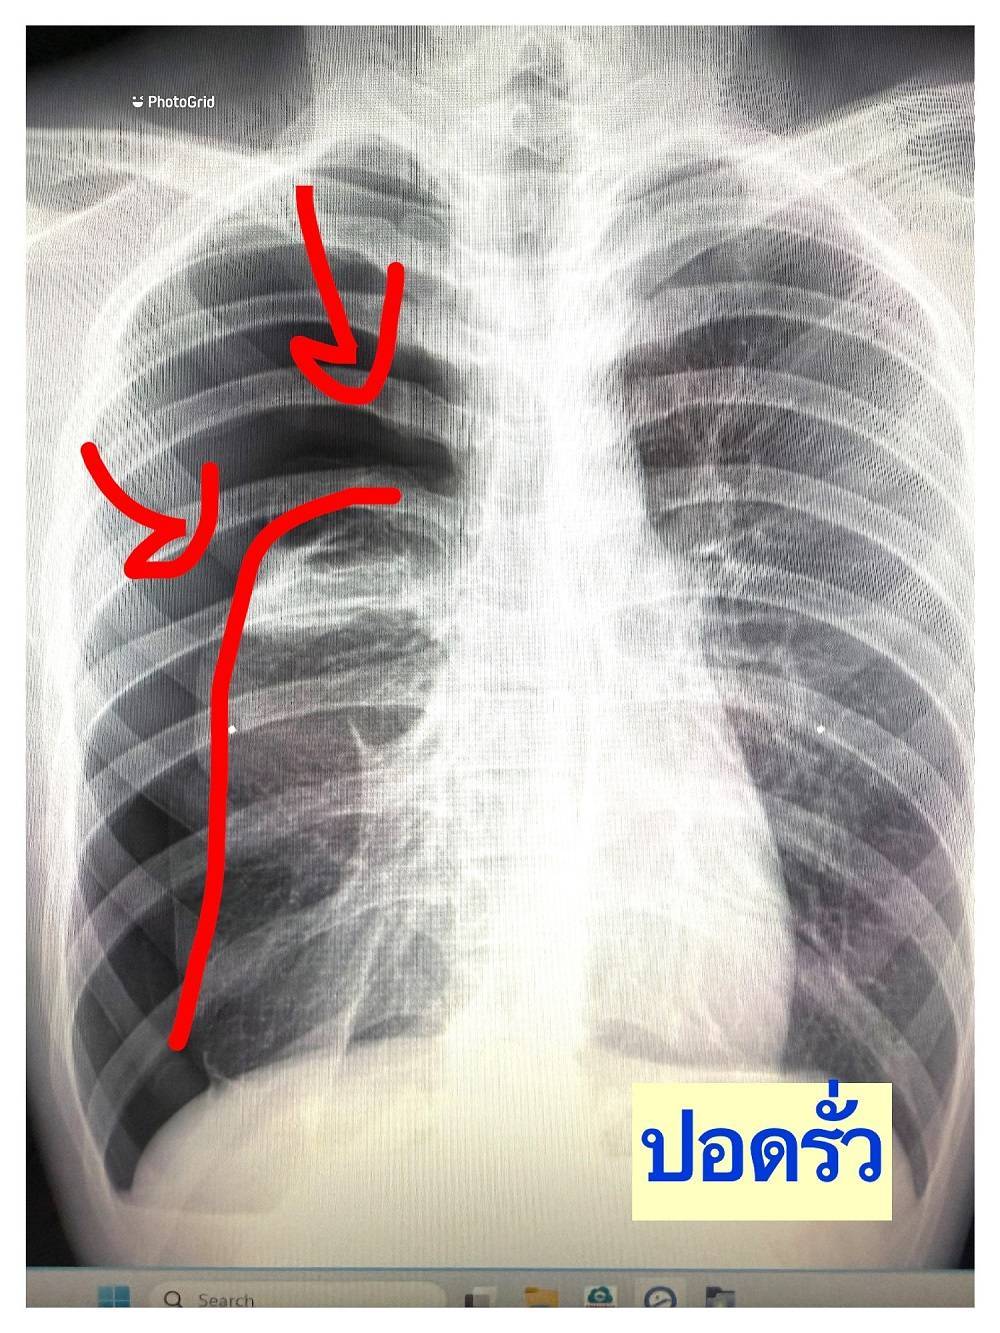

เมื่อไม่นานมานี้ ผมได้เจอเคสผู้ป่วยหญิงอายุราว 40 ปี มารักษาด้วยอาการเจ็บแน่นหน้าอก เป็น ๆ หาย ๆ อยู่หลายครั้ง แต่ไม่รู้สึกเหนื่อย รู้สึกว่าเมื่อมีอาการเจ็บหน้าอกทุกครั้ง มักจะเป็นในช่วงขณะมีประจำเดือน จึงมีอยู่ช่วงหนึ่งมีอาการเจ็บหน้าอกมากจึงรีบมาพบแพทย์ที่โรงพยาบาล หลังจากการตรวจสอบเอกซเรย์ พบว่าเป็นโรคลมรั่วในเยื่อหุ้มปอด ซึ่งมีโอกาสเสียชีวิตสูงหากไม่ทำการรักษา จึงรีบรับการรักษาตัวเข้าโรงพยาบาล

ซึ่งโดยปกติแล้วโรคลมรั่วในเยื่อหุ้มปอดจะมีจาก 3 สาเหตุ ได้แก่ 1) เกิดขึ้นได้เอง (Spontaneous Pneumothorax) มักเกิดในคนที่มีอายุน้อย ผอม สูง, 2) เกิดจากอาการมีโรคร่วม (Secondary Pneumothorax) พบในผู้ป่วยที่มีภาวะถุงลมโป่งพอง, 3) ลมรั่วขณะมีประจำเดือนที่เกิดจากช็อตโกตแลตซีสต์กระจายมา (Endometriosis Migration) โดยโรคลมรั่วขณะมีประจำเดือนนั้น โอกาสการเกิดโรคนี้ค่อนข้างยาก พบเจอไม่บ่อยมากนัก ผู้ป่วยเพศหญิงส่วนมากมักมาด้วยสาเหตุด้วยลมรั่วในปอดราว 20-30 % โดยภาวะลมในเยื่อหุ้มปอดชนิดนี้ เจอในเฉพาะเพศหญิงช่วงอายุ 32-37 ปีโดยอาจจะสัมพันธ์กับช็อตโกแลตซีสต์ในช่องท้อง หรือ มดลูกหรือ ไม่ก็ได้ โดยสาเหตุการเกิดของโรคนั้นยังไม่แน่ชัด ทั้งนี้อาการที่เกิดมักจะสัมพันธ์กับประจำเดือน ส่วนมากมักจะมีอาการเจ็บแน่นหน้าอกหรือหายใจไม่สุด ในบางครั้งอาจมีอาการเหนื่อย โดยมักจะเป็นในช่วง 24-72 ชั่วโมงนับตั้งแต่เริ่มมีประจำเดือนมาในวันแรก รศ.นพ.ศิระ เลาหทัย แพทย์ผู้เชี่ยวชาญศัลยศาสตร์ ทรวงอกเฉพาะทางด้านการผ่าตัดส่องกล้องในช่องทรวงอก โรงพยาบาลวชิรพยาบาล กล่าวว่าจากการวินิจฉัย ส่วนมากการทำ X-Ray หรือ ทำเอกซเรย์คอมพิวเตอร์ (CT Chest) หรือ MRI อาจพบได้ แต่อย่างไรก็ตามยังไม่มีการตรวจใดมีประสิทธิภาพที่สามารถวินิจฉัยโรคนี้ได้โดยตรง โดยในบางรายอาจพบถุงลมบริเวณยอดของปอดร่วมด้วยได้ (Lung Bleb) ในส่วนของการรักษาในโรคลมรั่วในเยื่อหุ้มปอดนี้ ประกอบด้วย 2 อย่าง ได้แก่1)การรักษาด้วยการผ่าตัด(ส่องกล้อง) และ2)การรักษาด้วยยา